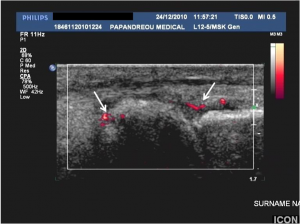

Κλινικά και παθολοανατομικά η ενθεσοπάθεια χαρακτηρίζεται απο φλεγμονή των τενοντοσυνδεσμικών στοιχείων στο σημείο της οστικής κατάφυσης. Υπερηχογραφικά ως ενθεσοπάθεια ορίζεται η ανώμαλη πάχυνση ενός τένοντα ή συνδέσμου ή/και η απώλεια της φυσιολογικής εσωτερικής ινιδιακής αρχιτεκτονικής του τένοντα στα σημεία πρόσφυσης στο οστό ή/ και παρουσία οστικών μεταβολών που περιλαμβάνουν ενθεσόφυτα, ανωμαλίες της οστικής παρυφής ή διαβρώσεις (εικ.7). Οι Frediani και συν25 στη μελέτη τους που